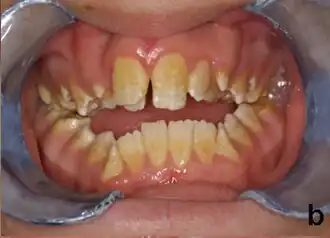

Amelogénesis imperfecta, tipo hipoplásico. Nótese la asociación de esmalte picado y mordida abierta.

Las personas afectadas con amelogenesis imperfecta tienen dientes con color anormal: amarillo, marrón o gris. Los dientes tienen un mayor riesgo de sufrir cavidades dentales y son hipersensitivos a los cambios de temperatura. Este desorden puede afectar cualquier número de dientes.